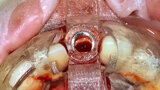

Fig. 24a: Depth control and rotational positioning were accurately

confirmed with the notch indicator on the template corresponding with the insertion tool (a). The occlusal view illustrated that the anti-rotational internal

conical–hexagonal connection was positioned towards the facial aspect (b).

Fig. 24b: Depth control and rotational positioning were accurately